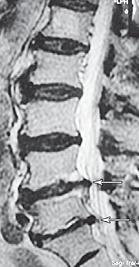

На МРТ № 40 наблюдается типичный пример развития стеноза второго типа в шейном отделе позвоночника. И аналогичная картина, только, в поясничном отделе позвоночника, отображена на МРТ № 41 Стеноз Стеноз позвоночного канала встречается довольно часто, во всяком случае в моей практике. В данной книге я уже упоминал о том, что стеноз спинномозгового канала (то есть его сужение) может вызывать серьёзные осложнения при течении таких заболеваний, как например, грыжи межпозвонкового диска. Для лучшего понимания происходящих процессов давайте в общих чертах рассмотрим, что такое стеноз и чем он опасен. Итак, стеноз — это врождённое или приобретённое аномальное сужение просвета какого-либо полого органа (пищевода, кишечника, кровеносного сосуда и др.) или отверстия между полостями (например, при пороках сердца). Стеноз позвоночного канала характеризуется его патологическим сужением. Исходя из анатомо-физиологических особенностей позвоночного канала, который является вместилищем и в тоже время охранным футляром для спинного мозга, даже незначительное его сужение может оказаться фатальным для спинного мозга. К примеру, при развитии абсолютного стеноза позвоночника спинной мозг может быть компримирован (сжат) вместе с артериями. В свою очередь это неизбежно ведёт к развитию ишемии (от греч. ischo — «задерживаю, останавливаю» и haima — «кровь»; уменьшение кровоснабжения участка тела, органа или ткани вследствие ослабления или прекращения притока к нему артериальной крови) тех участков спинного мозга, где блокировано кровоснабжение сдавленными сосудами. Ещё в конце XIX века, а точнее в 1880 году, в своей работе М. Литтен отметил, что спинной мозг более чувствителен к ишемическим повреждениям и недостатку кислорода, чем другие ткани организма. А вот отечественному невропатологу, ученику В. М. Бехтерева и одному из первых нейрохирургов, Л. М. Пуссепу в 1902 году удалось в эксперименте на животных показать, что даже непродолжительная ишемия спинного мозга влечёт за собой некроз (отмирание) нервных клеток передних рогов спинного мозга. Если добавить к этому ещё и неизбежное нарушение ликвородинамики и развития (вследствие сдавления оболочек спинного мозга) эпидурита и арахноидита, то возникновение болевых, корешковых и сосудистых синдромов (в виде миелоишемии, радикулоишемии или миелорадикулоишемии) становятся вполне объяснимыми и понятными. Исходя из классификации, предложенной доктором I. Stephen, которой пользуется большинство авторов в своих работах, стеноз позвоночного канала позвоночника, как я уже упоминал, бывает двух типов. Тип первый — врождённый, или как его ещё называют идиопатический, то есть беспричинный (неизвестного, неясного происхождения). Второй тип — приобретённый, возникший вследствие дегенеративно-дистрофических процессов в позвоночнике, посттравматический или обусловленный другими причинами, которые привели к стенозированию (сужению) позвоночного канала. Например, грыжа межпозвонкового диска даже центральной локализации, имеющая размер всего 6 мм в дорсальном направлении в поясничном отделе позвоночника с сагиттальным размером спинномозгового канала в 15 мм приводит к формированию абсолютного стеноза второго типа (приобретённого) и может вызвать серьёзные осложнения. А при стенозе первого типа (врождённого, см. МРТ № 43), к примеру с сагиттальным размером спинномозгового канала в поясничном отделе 12 мм, даже трёхмиллиметровая протрузия межпозвонкового диска может привести к развитию слабости в ногах, мышечной атрофии или, как описывал данные состояния Dejerine ещё в 1911 г., «перемежающейся хромоте спинальной природы». |